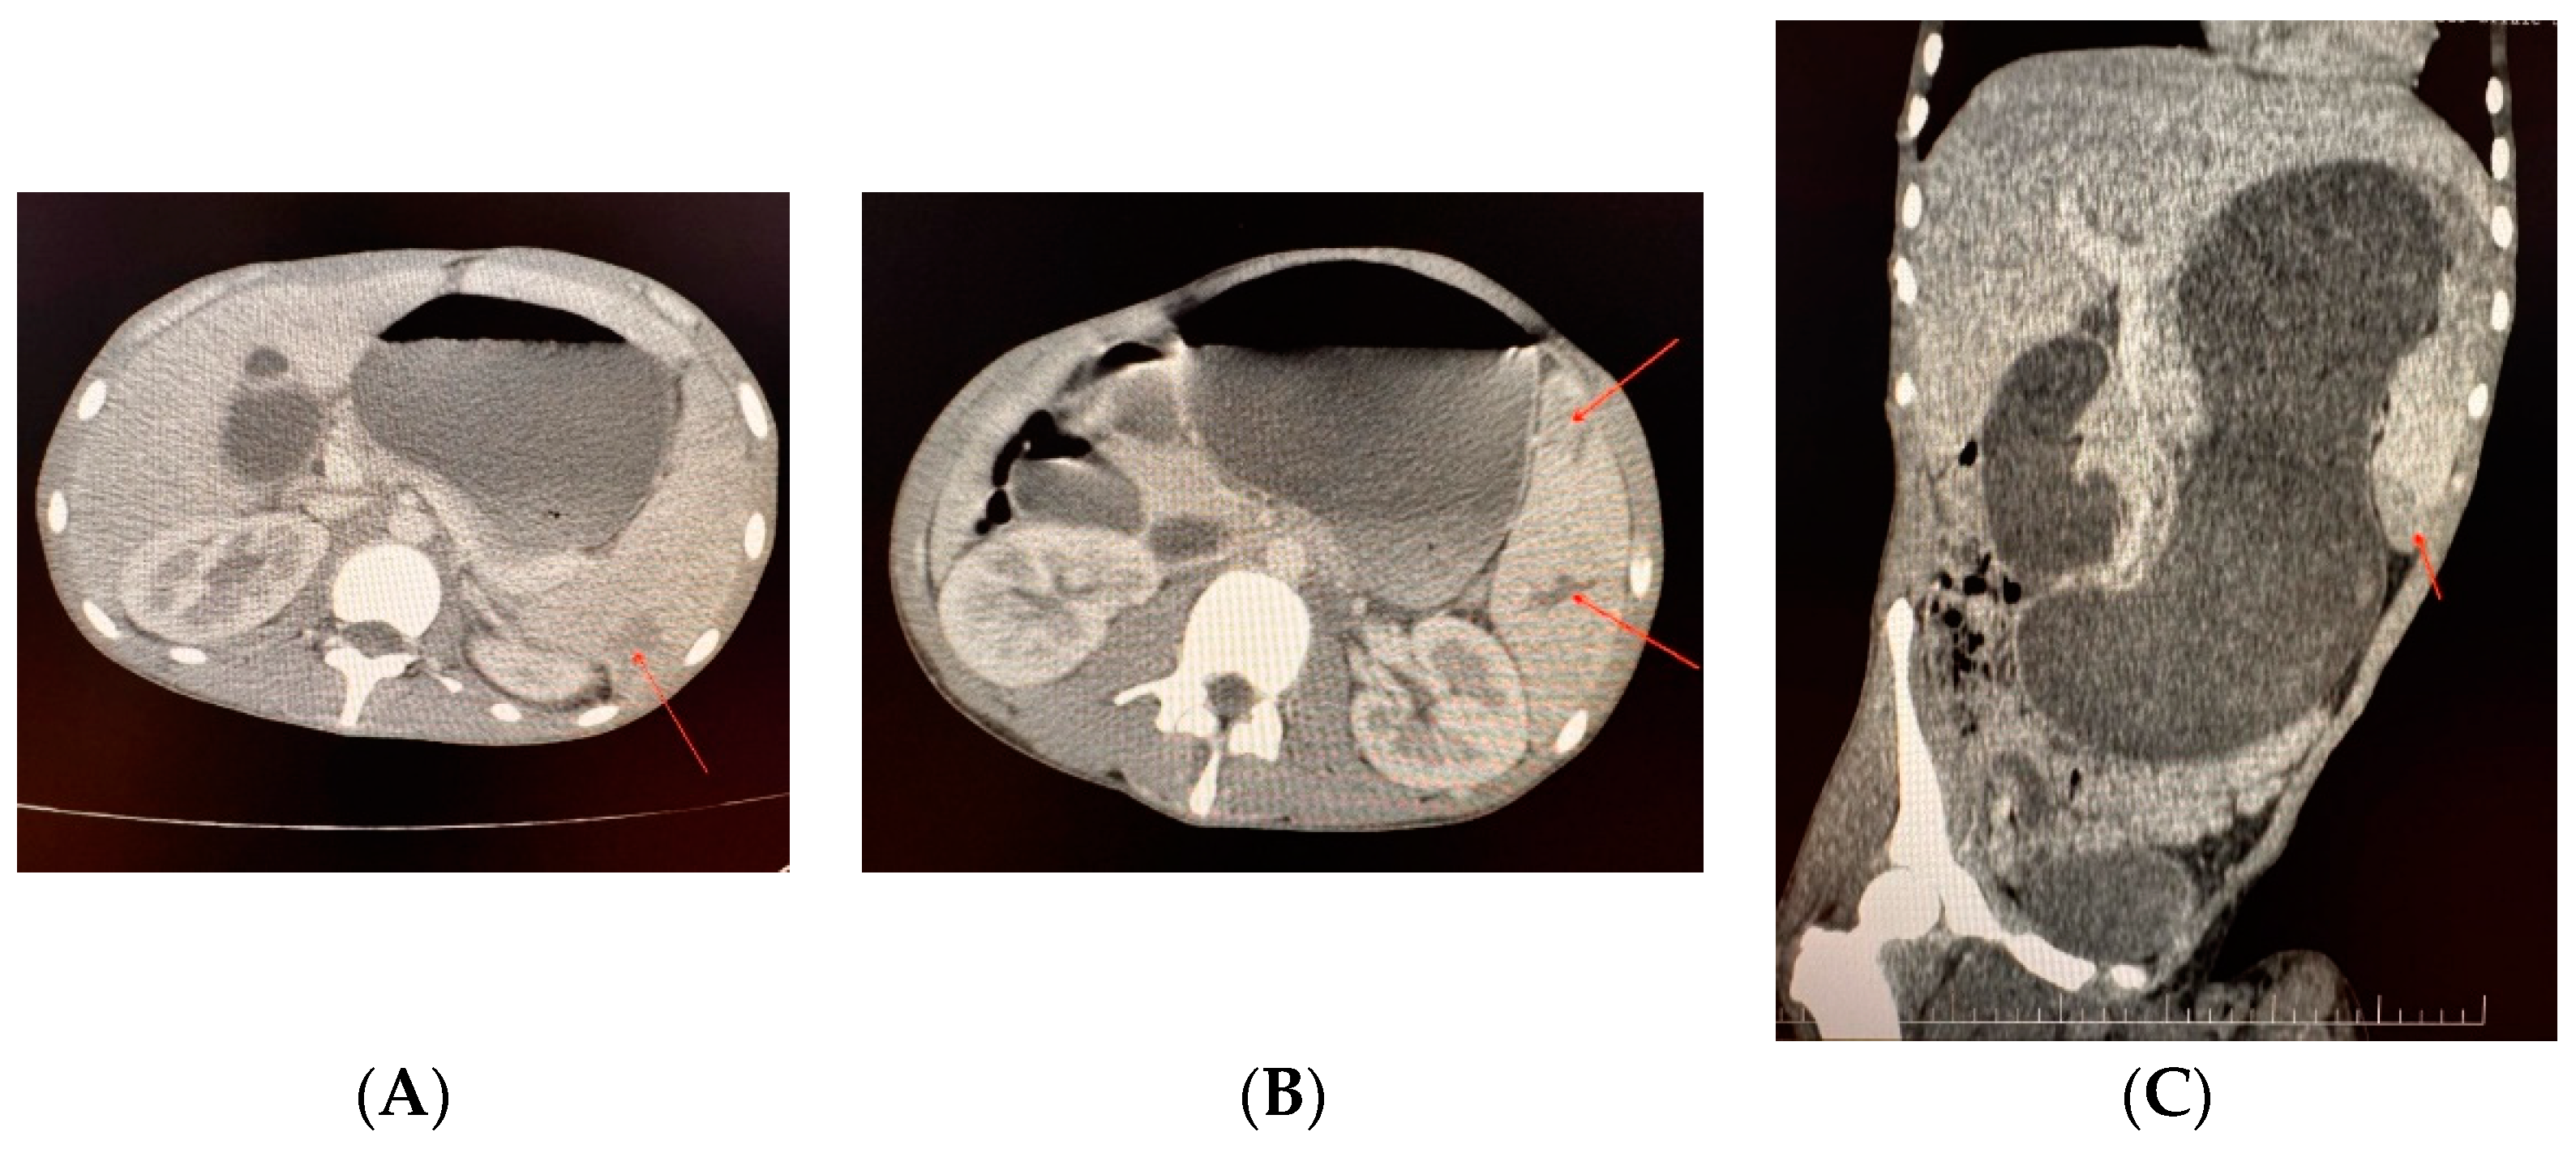

| Case 3. 19-years-old male with severe haemophilia B | -chronic viral hepatitis C | -intense pain in the left hypochondrium, epigastrium, and mesogastrium -massive abdominal distension -splenomegaly with two hematomas in the mid-body and inferior pole, and suspected rupture in two times -left elbow and calf hematoma with cutaneous necrosis | -splenectomy -evacuation of the left elbow hematoma -elbow skin necrosis excision (defect 6/4 cm) followed by partial covering, with skin collected from the anterolateral and 1/3 middle side of the left thigh -evacuation of the left calf hematoma, approximately 400 mL sero-hematic liquid + clots (fibrillar rupture of internal gemini muscles) | ~1500 mL (4 units pRBCs) | ~32,763.70 € (92.80% for plasma-derived FIX concentrate) | -acute functional gastric dilatation due to pyloric spasm, with evacuation of 2.5 L of gastric stasis liquid -hematoma at the inferior pole of the surgical wound. | Good, discharge after 27 days |